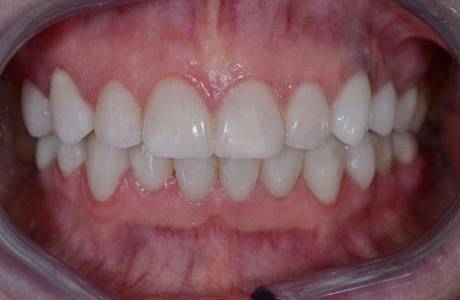

После лечения

На верхней челюсти было принято решение установить E-max коронки.На нижней челюсти E-max виниры. Пациент полностью доволен свой новой красивой улыбкой.